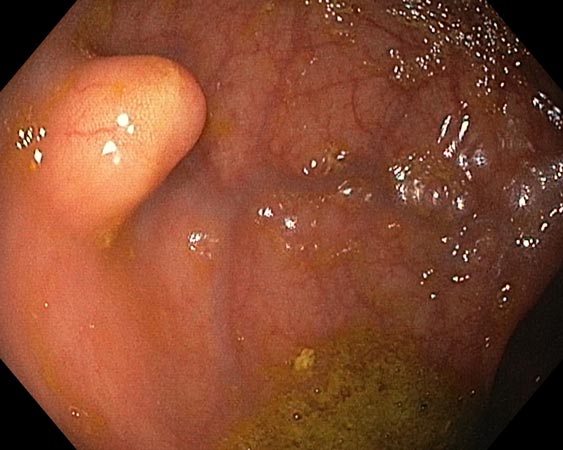

Проводили удаление образования единым блоком для проведения патоморфологического исследования. В случае моноблочной и фрагментарной резекции образования использовали диатермическую петлю SD-210U-25. Сведение краёв клипсами выполняли только после диссекции подслизистых образований (рис. 3–6).

Рис. 3. Частично окаймляющий разрез

Рис. 4. Диссекция в подслизистом слое

Рис. 5. Дефект после удаления

Рис. 6. Клипирование дефекта